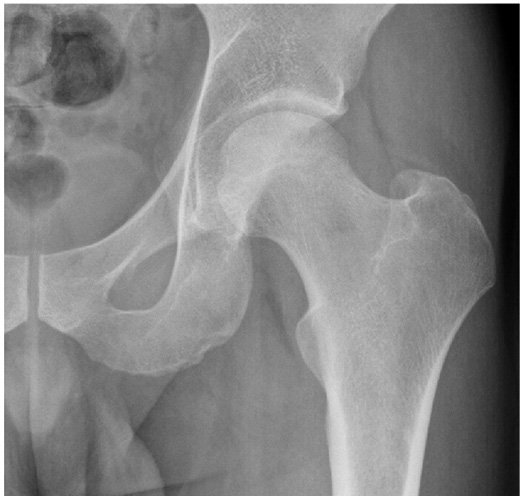

Tuberculosis of the hip — advanced joint destruction

The main treatment is non-operative with multiple drugs. Multi-drug-resistant TB accounts for 27% of cases. TB causes destruction of the articular cartilage, dislocation, protrusio, avascular necrosis, and fibrous ankylosis. Joint debridement and removal of unhealthy tissue can both improve healing and optimise joint function. Persistent pain and stiffness can be treated with arthrodesis, joint excision, or total joint replacement.